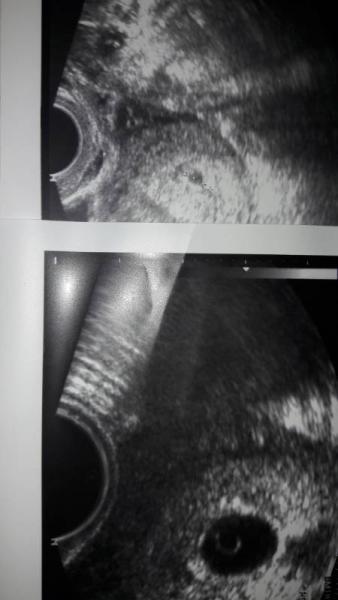

Ihr Lieben, ich brauche eure Meinung. Letzte Woche Mittwoch war ich bei meinem ersten Ultraschall. Rechnerisch 6+1. Man sah nur eine kleine fruchthöhle. Der Arzt war leicht beunruhigt, da man schon viel mehr sehen müsste, aber er sagte vielleicht hat sich der ES verschoben. Aber man merkte er ging eher vom negativen aus. Gestern dann der nächste Kontrolltermin. Ich erfuhr, dass die abgenommenen Werte im Blut zu dem im Ultraschall gesehenen passen. Gestern zeigte sich dann eine deutlich größere fruchthöhle mit Dottersack - selbst für mich als Laie zu erkennen. Ich war so glücklich, weil ich nicht damit gerechnet habe, dass sich etwas tut. Der Arzt war sehr pessimistisch. Sagte da kein Embryo da ist rät er zur Ausschabung. Am Freitag soll ich noch ein mal zur Kontrolle kommen. Da ich schon vor über 3 Wochen positiv getestet habe müsste man viel mehr sehen, ich solle mich damit auseinander setzen. Jetzt bin ich sehr verunsichert, weil der Fortschritt für mich so deutlich war dachte ich es sei alles in Ordnung erstmal. Hat jemand ähnliche Erfahrungen gemacht? Hier das Bild von Ultraschall 1 und 2.

Bild zu Ist es noch möglich? - Schwanger - wer noch? Rund um die Schwangerschaft

Hallo, also leer ist die Fruchthöhle auf dem 2. UltraschallBild nicht. Ich sehe da einen Dottersack. Wirklich aussagekräftig wäre nun eine zweite BlutAbnahme gewesen um zu sehen wie sich der hcg-Wert entwickelt hat. Die Höhe des hcg alleine besagt so gut wie nichts, nur die Entwicklung dessen. Ich würde nochmal mindestens eine Woche abwarten und hätte auch gerne einen Vergleichswert für das hcg. Vermutlich ist die Schwangerschaft leider nicht intakt. Aber der aktuelle Stand wäre mir für eine Ausschabung noch zu ungenau!!! Warten schadet da nichts! Lieber eine Woche zu lang gewartet als sich sein Leben lang fragen ob es richtig war. Drücke dir die Daumen...!! Hannah

Als ich von meiner ss erfahren habe war ich in der 8ssw. Und der Ultraschall sah genau so aus wie dein zweites Bild. Und auch noch kein Herzschlag zu sehen. Genau eine Woche später müsste ich wieder hin und man sah den Herzschlag und Sie hatte sich auch weiter entwickelt. Jetzt wird meine kleine 1jahr alt. Ich bin ein gehen ausschabung. Wenn es bleiben möchte dann bleibt es wenn nicht wird es auch alleine weg gehen. Und mein Arzt war darmals überhaupt nicht besorgt wegen dem Ultraschall und meinte nur dass es wieder aufholen wird. Und das tat sie auch. Also ich würde dir raten nichts zu überstürzten :)